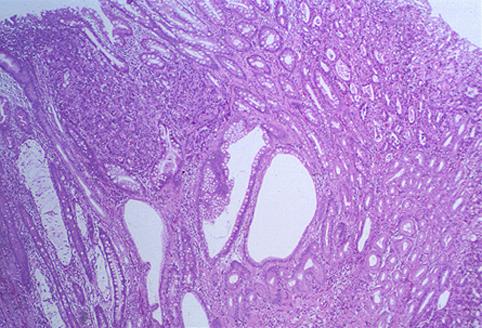

疾病(病理主体)的分类恶性上皮性肿瘤/腺癌

部位(按器官分)胃(部位)/前庭

检查方法病理切片(微观)

肿瘤的肉眼分类0型(表在型)/IIa型(IIa+IIc)

肿瘤最大直径25~29

肿瘤的深度m